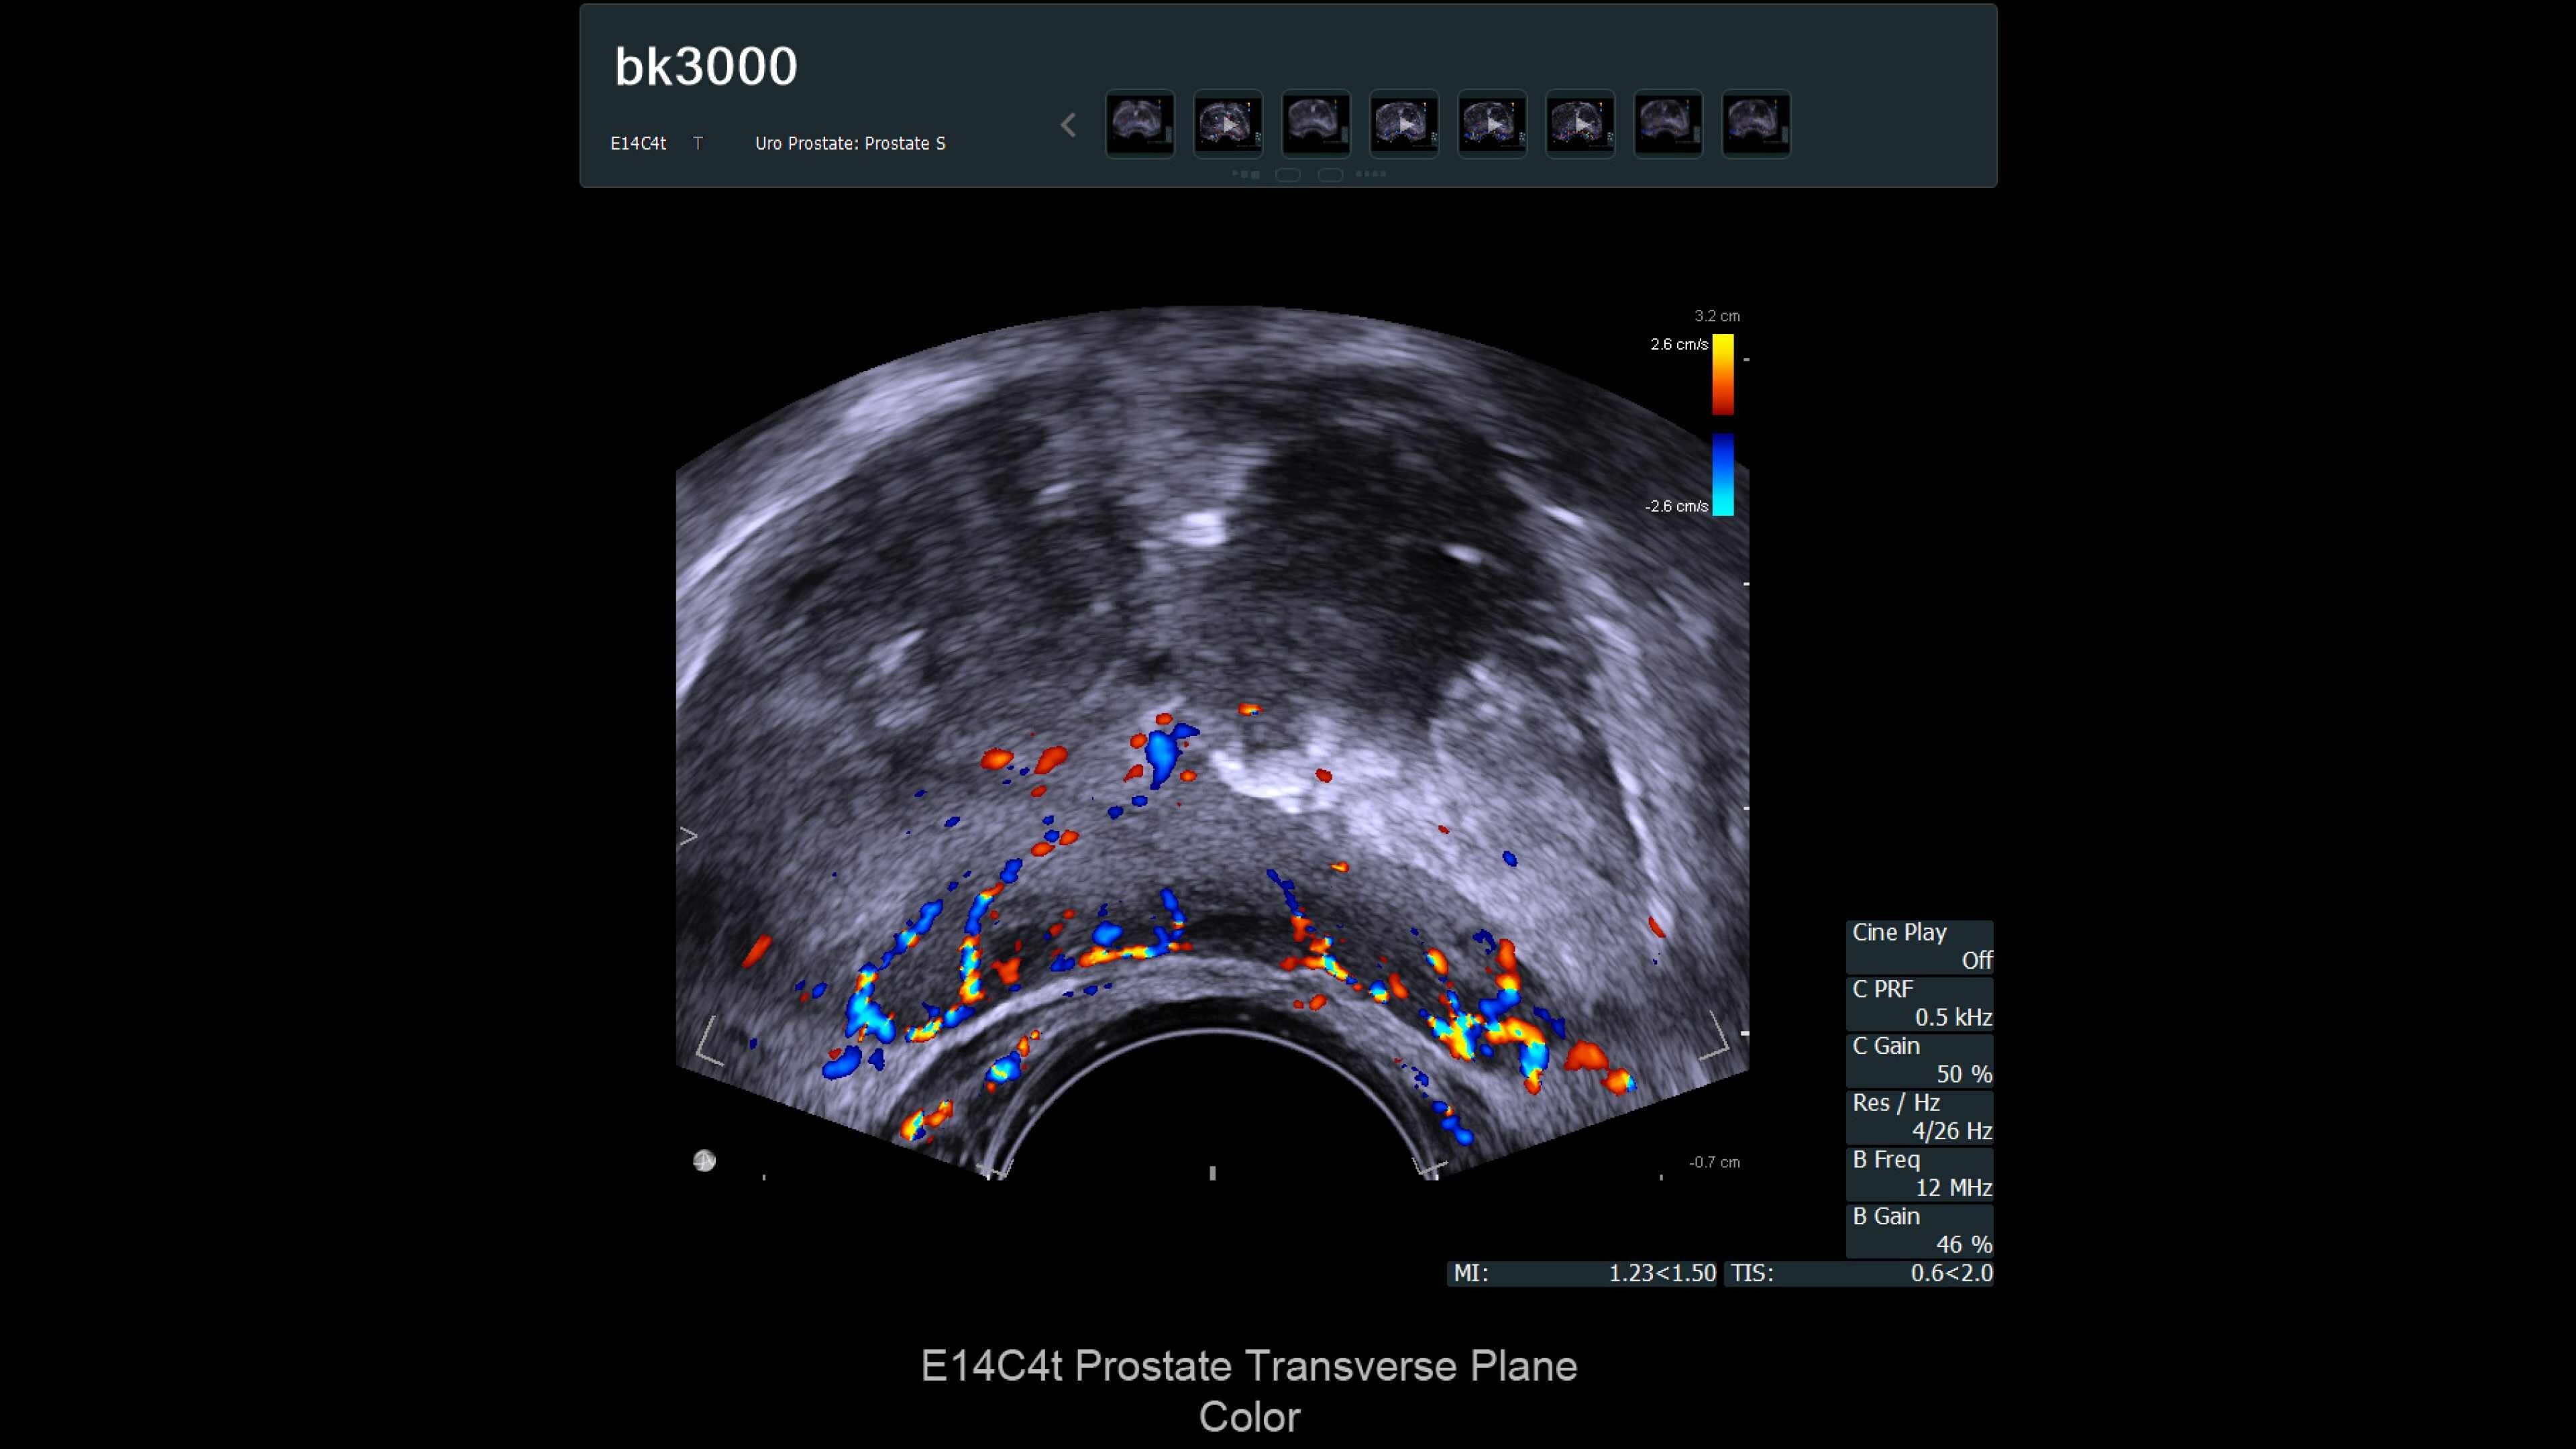

The bk3000 ultrasound machine offers ultra high-resolution imaging for urology, including exceptional prostate, kidney, bladder, and testes imaging. It features real-time, high-definition prostate images, elastography for targeted biopsies, and a unique Triplane transducer for simultaneous biplane and endfire imaging. The system enhances lesion targeting with fusion-guided biopsies, combining MRI and ultrasound for precision prostate biopsies. Advanced imaging features and dedicated transducers improve visualization and treatment confidence during prostate interventions.